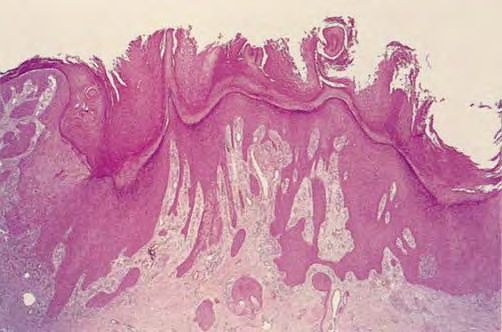

Poroma=شزن=تورم بسبب إفراز غدي POROMA The term poroma refers to a group of rare cutaneous appendage tumors composed of cells (cuticular and poroid cells) similar to those of the acrosyringium. Poromas are traditionally subcategorized histopathologically based on their location in relation to the epidermis into three main variants; namely, hidroacanthoma simplex, eccrine poroma, and […]